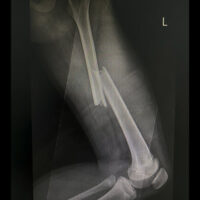

Not all fractures are alike. Simple fractures, where the bone breaks cleanly and stays aligned, often heal quickly with a cast or splint. In contrast, more severe injuries, like compound fractures, where the bone pierces the skin, or comminuted fractures, where the bone shatters into multiple pieces, require surgery, hardware such as plates or rods, and extensive physical therapy.

The location of the break also plays a big role. For instance, bones in the hands, wrists, and ribs often heal faster due to better blood flow and smaller bone size. Larger bones, such as the femur or pelvis, typically take longer to mend because of their size, the stress they bear, and the complexity of surrounding muscle and tissue structures.